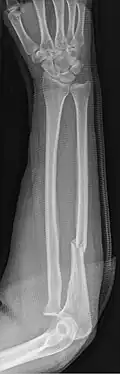

An ulna fracture is a break in the ulna bone, one of the two bones in the forearm.[2] It is often associated with a fracture of the other forearm bone, the radius.[1][3]

Fractures of the ulna can occur at different levels of the bone: near the wrist, in the middle or near the elbow.[2] The fracture may be confined to the ulna or accompanied with damage to the radius or the wrist or elbow joints.[2]

- Nightstick fracture is a fracture of the middle portion of the ulna without other fractures.[1]

- Monteggia fracture - a fracture of the near to elbow end of the ulna with the dislocation of the head of the radius at the elbow joint.[2]